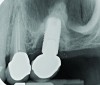

Radiograph of a mandibular left first molar implant in a 61-year-old man taken 2 years after the implant’s placement. No bone loss beyond physiologic remodeling has occurred.

Figure 5

Four weeks following nonsurgical treatment, the area is healthy as probing depths are now shallow and bleeding is absent. Treatment involved scaling of the area, which removed all plaque and a slight amount of cement, and irrigation with an anti-inflammatory hydrogel.

Figure 7